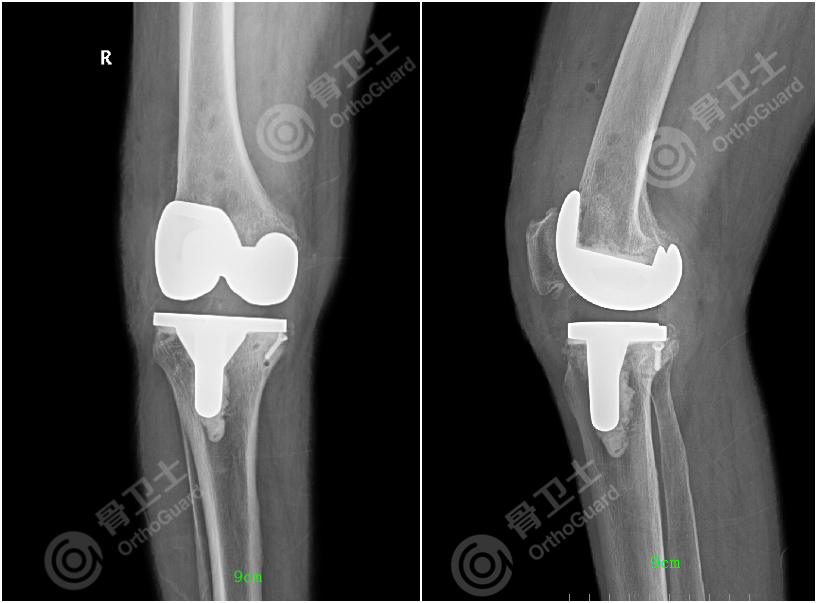

▲患者术后X线片

完善术前准备后,患者在椎管内麻醉+股神经阻滞麻醉下行右膝关节全膝置换术。术后给予静脉静滴止痛药,联合股神经阻滞,术后镇痛效果良好,患者基本在无痛下进行术后功能锻炼,效果良好。